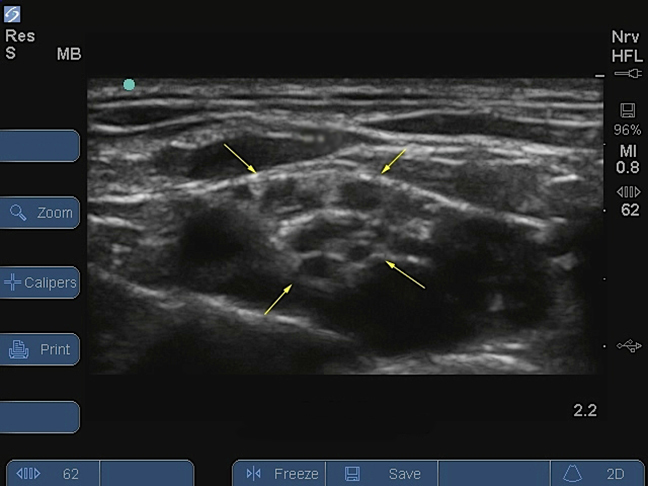

M-Turbo:锁骨上臂丛等级 - 2 注射后图像

锁骨上臂丛入路

黄色箭头:神经